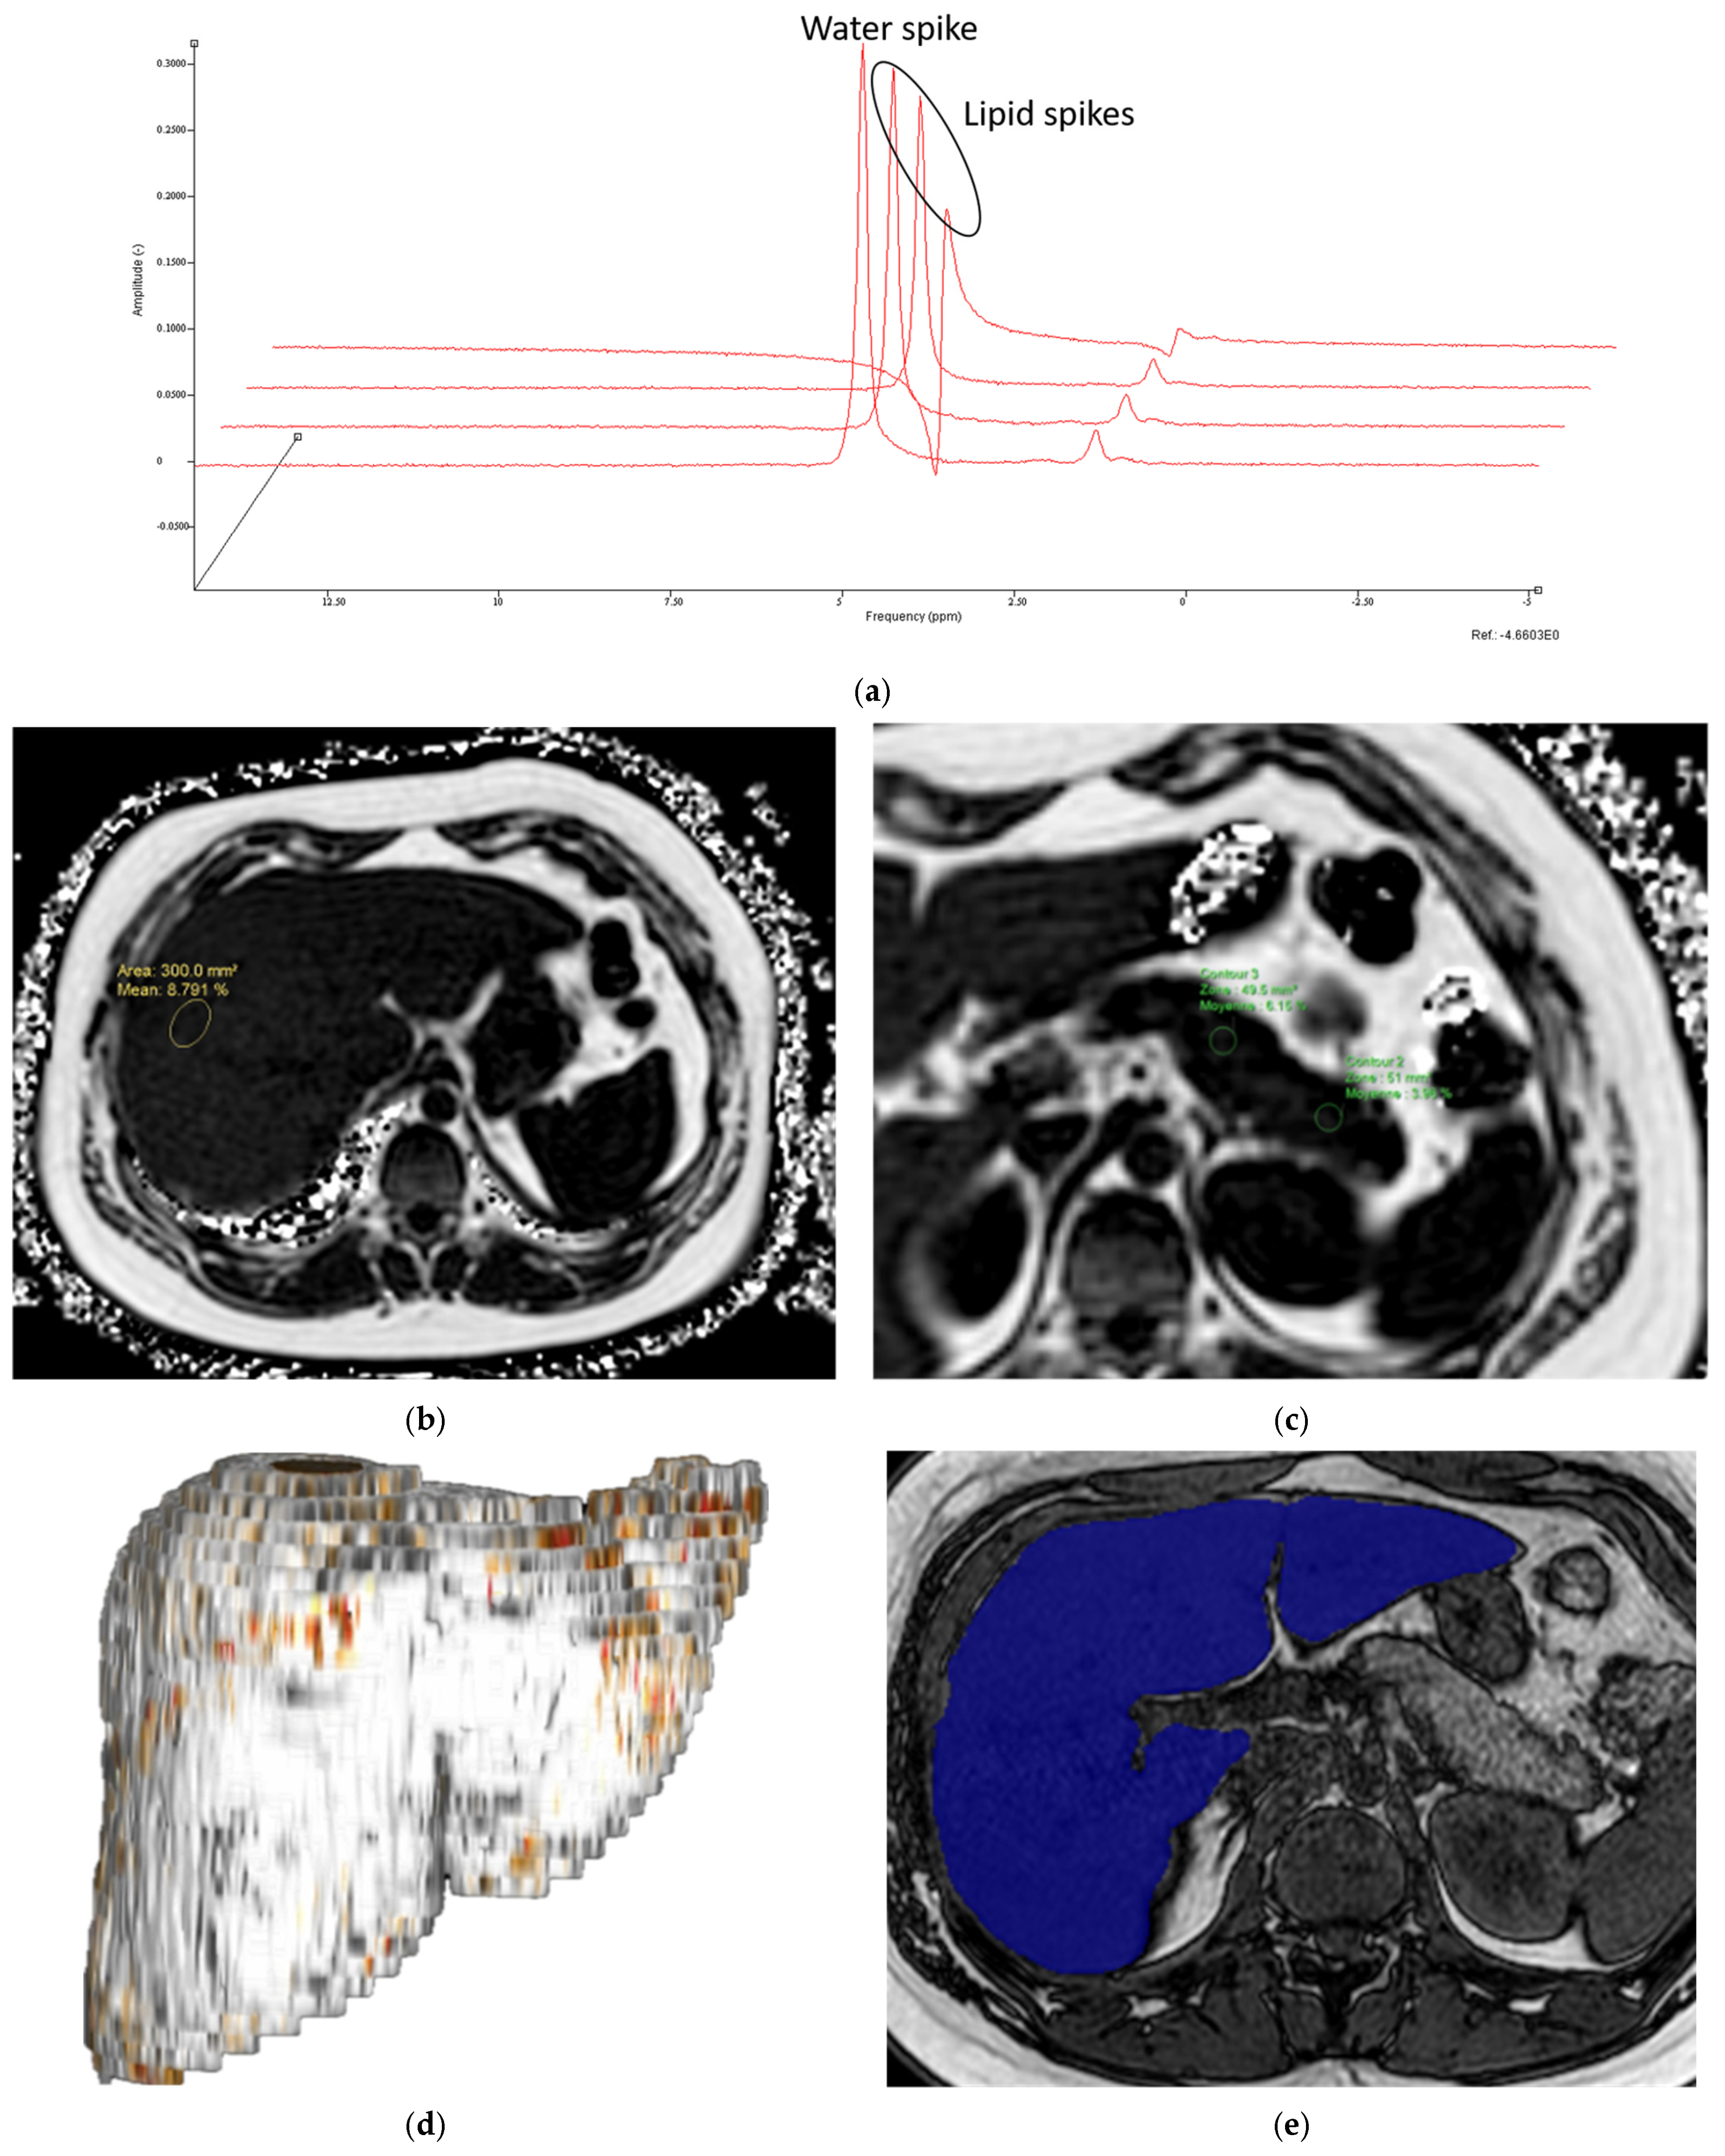

- MR Spectroscopy

- MRI-PDFF

- Liver and pancreas volumes